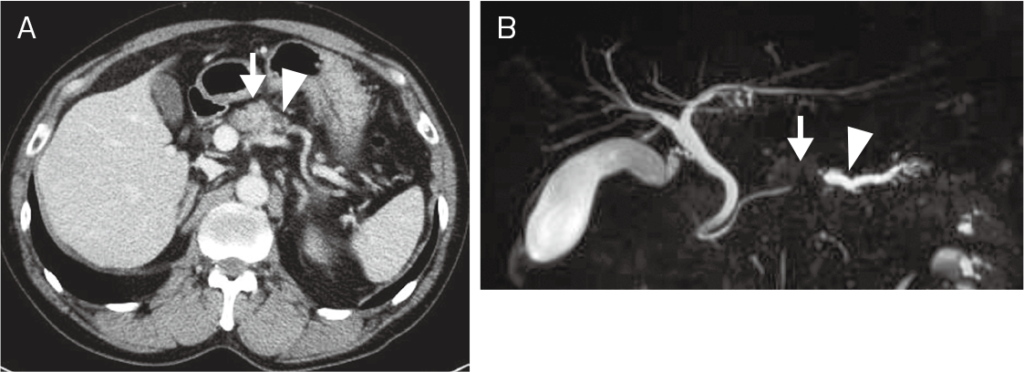

In our clinical practice, we often receive consultations from patients whose benign tumor was considered as a malignant tumor and were about to undergo a lung or breast resection. On the other hand, there are cases where cancer and cerebral infarction were overlooked due to oversight in imaging tests. Misdiagnoses and oversights often occur in imaging tests, but please use our service to prevent them.

- Liver cancer (hepatic carcinoma), Bile duct cancer, Gallbladder cancer, Pancreatic cancer